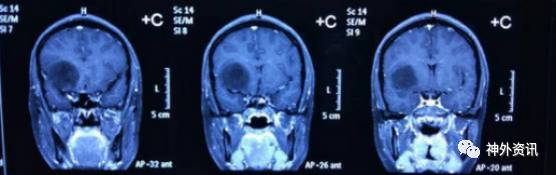

术前MR